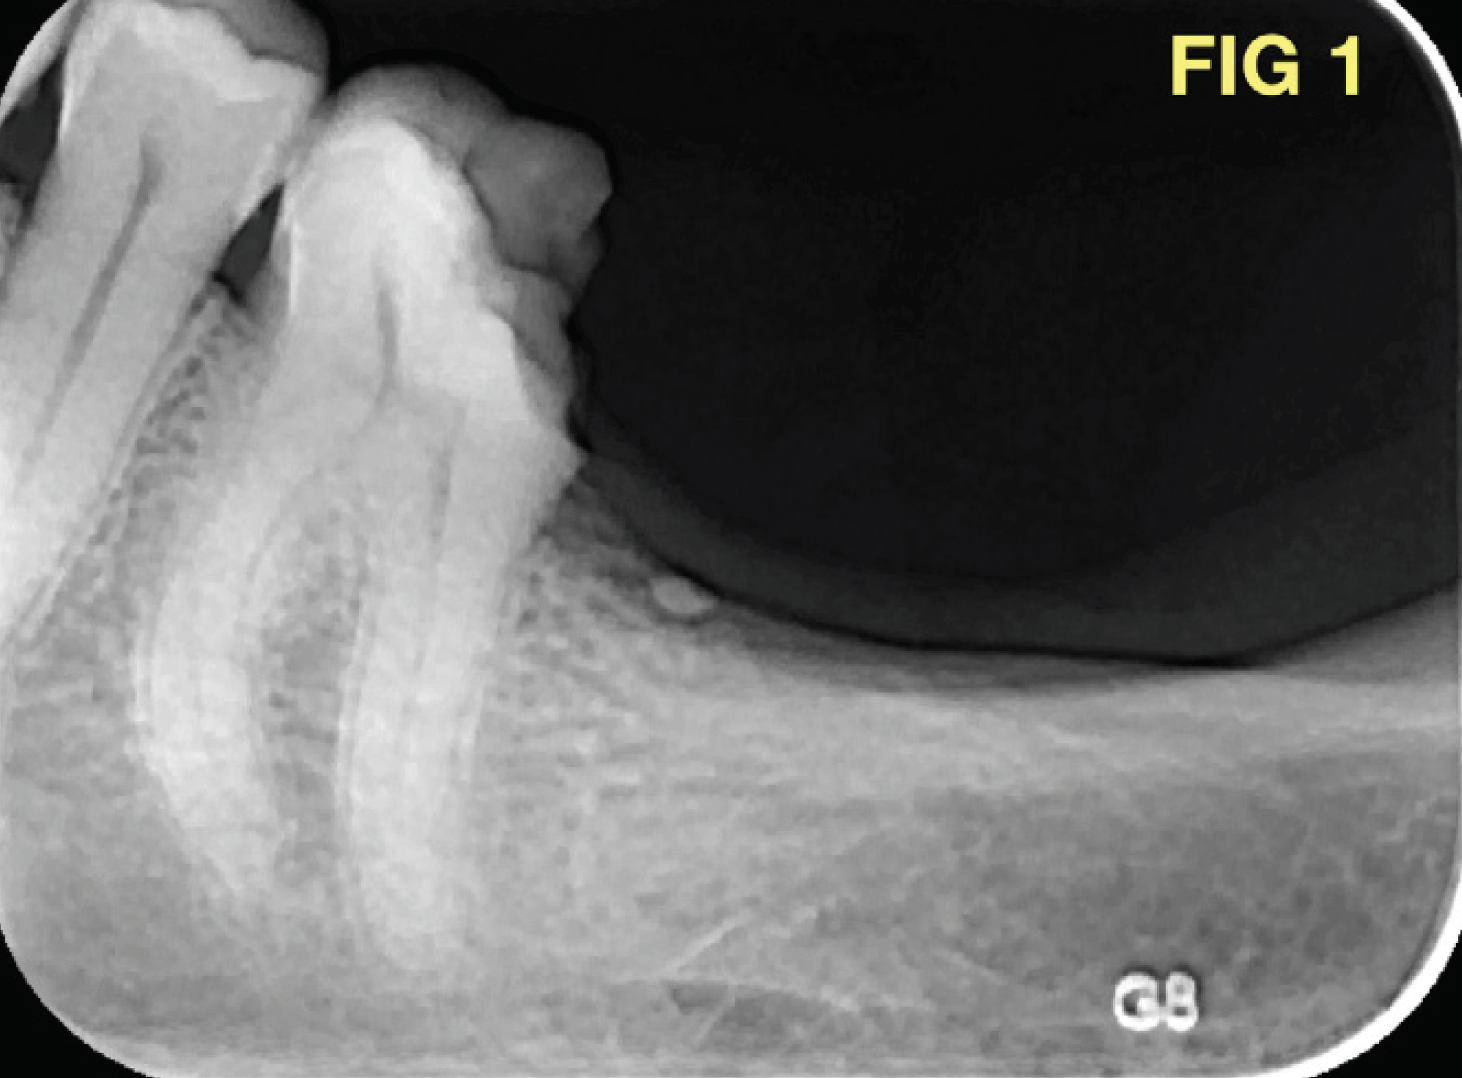

Eine 42-jährige Patientin klagte über starke Schmerzen im unteren Seitenzahnbereich nach einer Kronenfraktur. Die klinische und radiologische Untersuchung zeigte eine disto-okklusale Karies am Zahn 36 (Abb. 1) und ein freigelegtes distales Pulpenhorn. Der Zahn reagierte hochsensibel auf den thermischen Kältetest. Es wurde eine akute Pulpitis diagnostiziert. Die Patientin akzeptierte den Vorschlag einer endodontischen orthograden Behandlung.